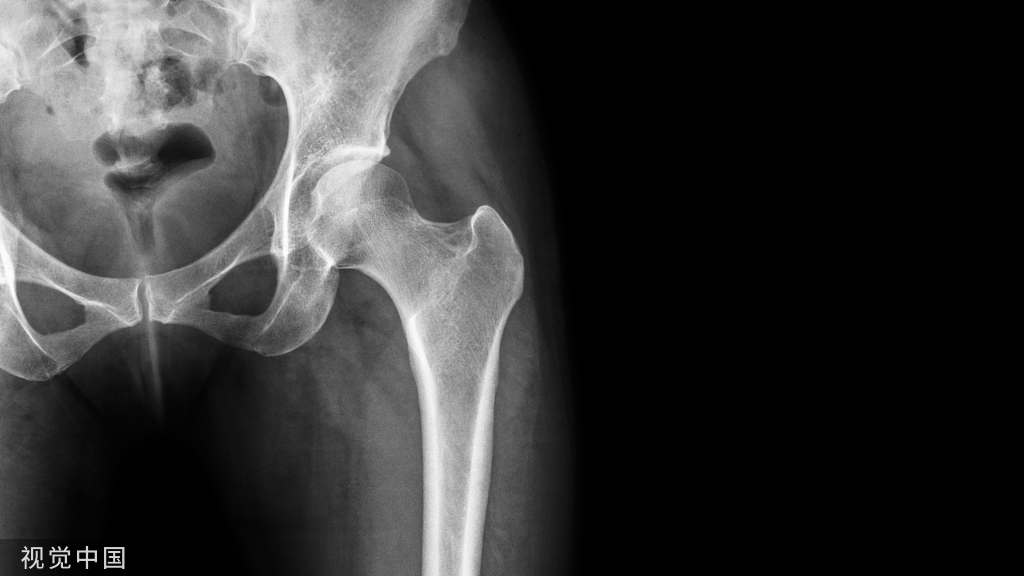

髋关节的解剖

髋关节(髂股关节)被分类为滑液球窝关节。该关节由股骨头与骨盆带的关节窝(髋臼)连接组成,骨盆带由髂骨、坐骨和耻骨三块骨构成。毋庸置疑,髋关节是人体最灵活的关节之一,因为它可以发生多轴运动。考虑到其固有的深髋臼(窝)结构,此关节具有很大的稳定性和活动性。

髋关节解剖(髂股关节)

髋关节可能的运动在个体之间会有所变化,但是髋关节正常的关节活动度如下:屈曲0°-130°,伸展0°-30°,内旋0°-35°,外旋0°-45°,外展0°-45°,内收°-25°。